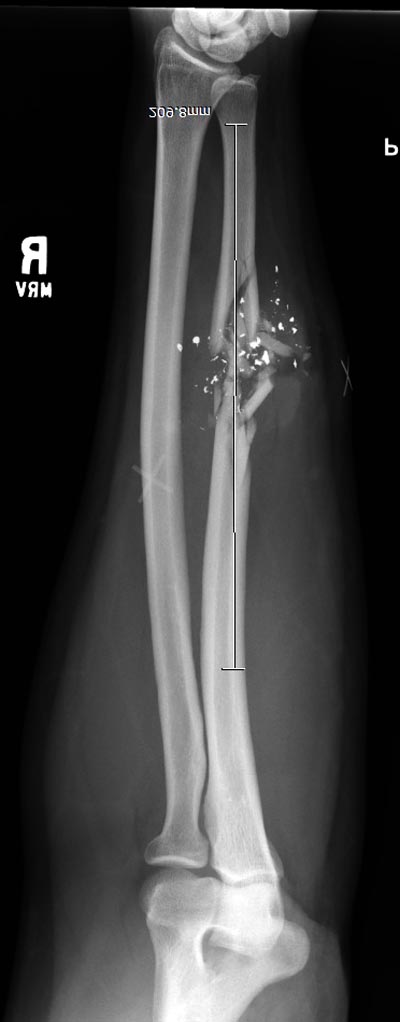

Здесь примеры: двоюродные братья с ранением предплечья, у одного

локтевая, а у второго лучевая. В следующее утро локтевая фиксирована без

обнажения фокуса травмы из небольших доступов, а второй из обычного

волярного доступа. А клинический снимок из прошлых операций...